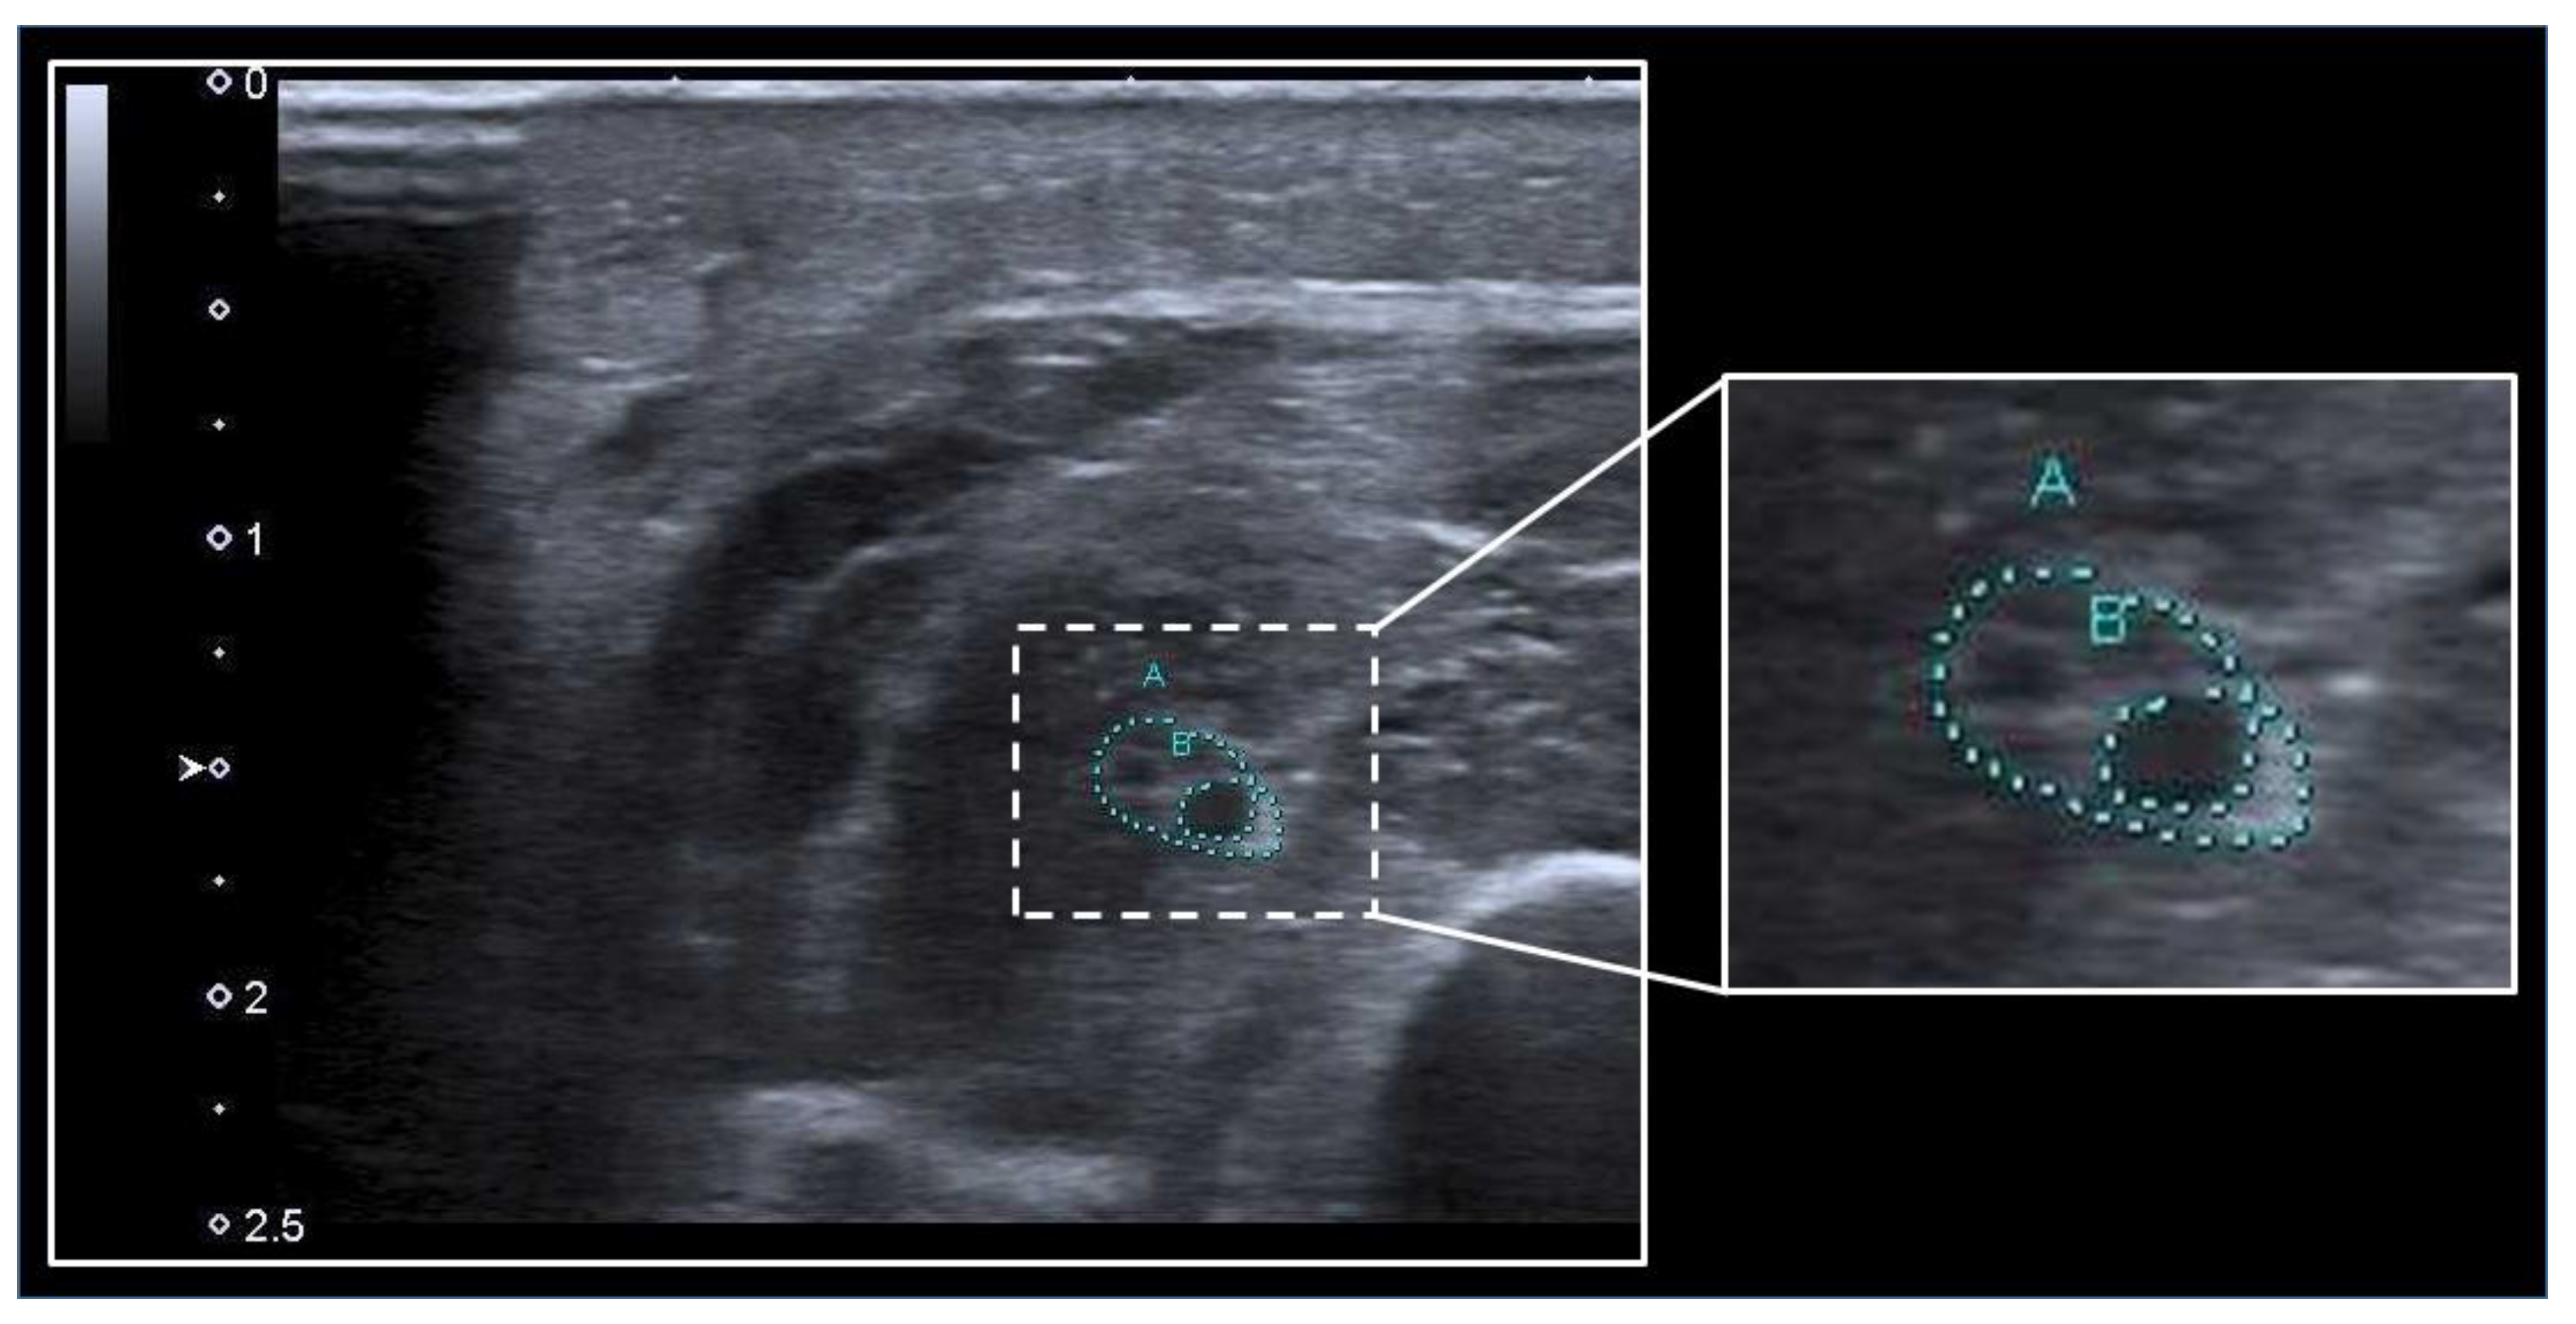

- Katakis, S.; Barotsis, N.; Kakotaritis, A.; Tsiganos, P.; Economou, G.; Panagiotopoulos, E.; Panayiotakis, G. Muscle Cross-Sectional Area Segmentation in Transverse Ultrasound Images Using Vision Transformers. Diagnostics 2023, 13, 217. [Google Scholar] [CrossRef]

- Katakis, S.; Barotsis, N.; Kakotaritis, A.; Economou, G.; Panagiotopoulos, E.; Panayiotakis, G. Automatic Extraction of Muscle Parameters with Attention UNet in Ultrasonography. Sensors 2022, 22, 5230. [Google Scholar] [CrossRef]

- Ritsche, P.; Wirth, P.; Franchi, M.V.; Faude, O. ACSAuto-semi-automatic assessment of human vastus lateralis and rectus femoris cross-sectional area in ultrasound images. Sci. Rep. 2021, 11, 13042. [Google Scholar] [CrossRef]